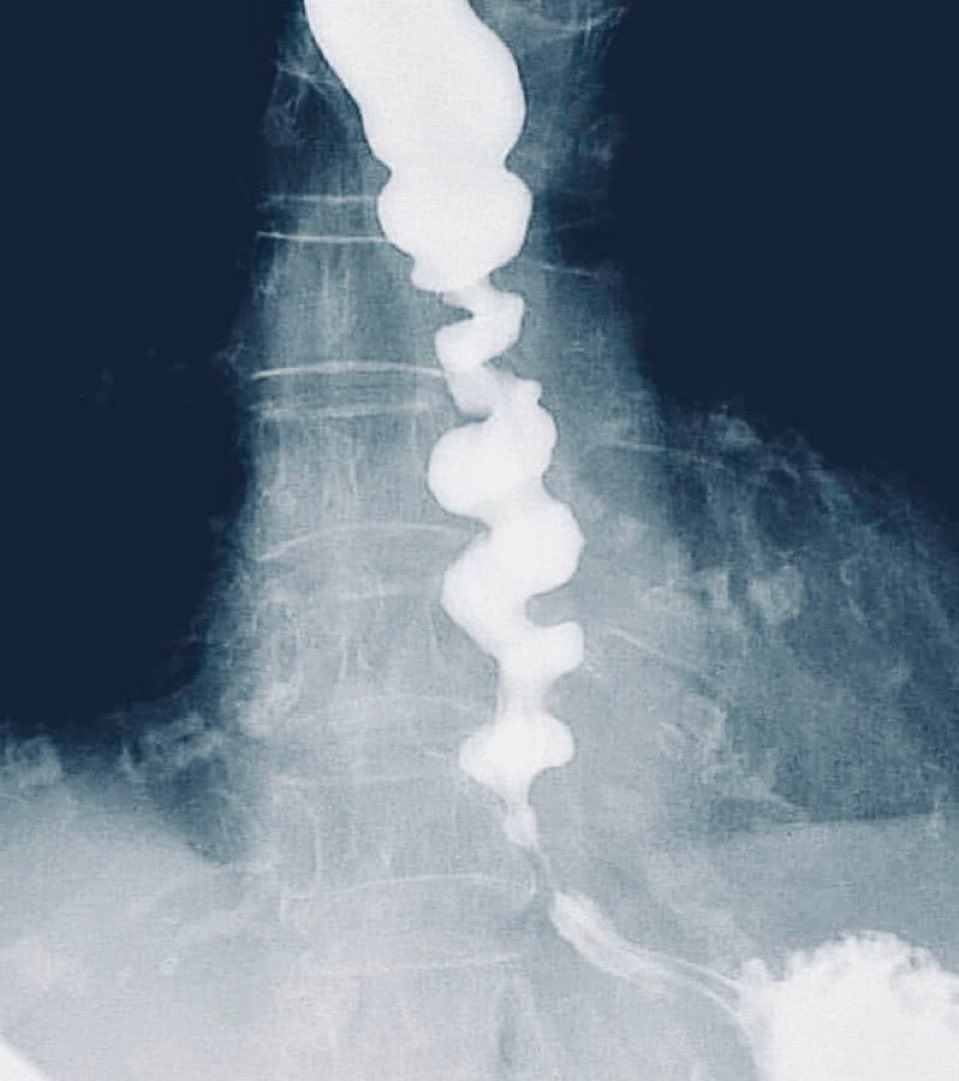

@docxusofficial

DocXus

4 days

Recurrent dysphagia with chest pain what’s the condition ❔

30

38

342